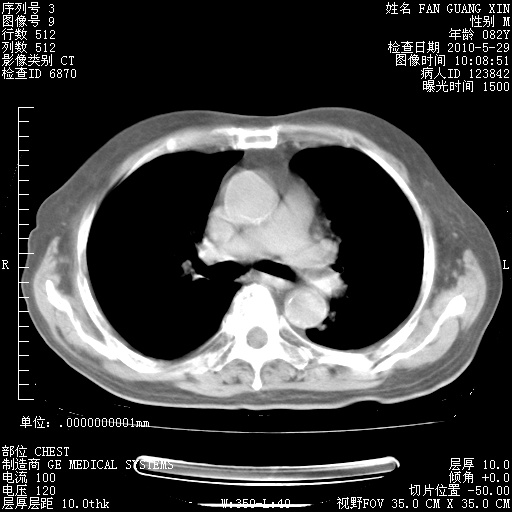

治疗3周后的肺部CT纵隔窗

再治疗10天后的肺部CT